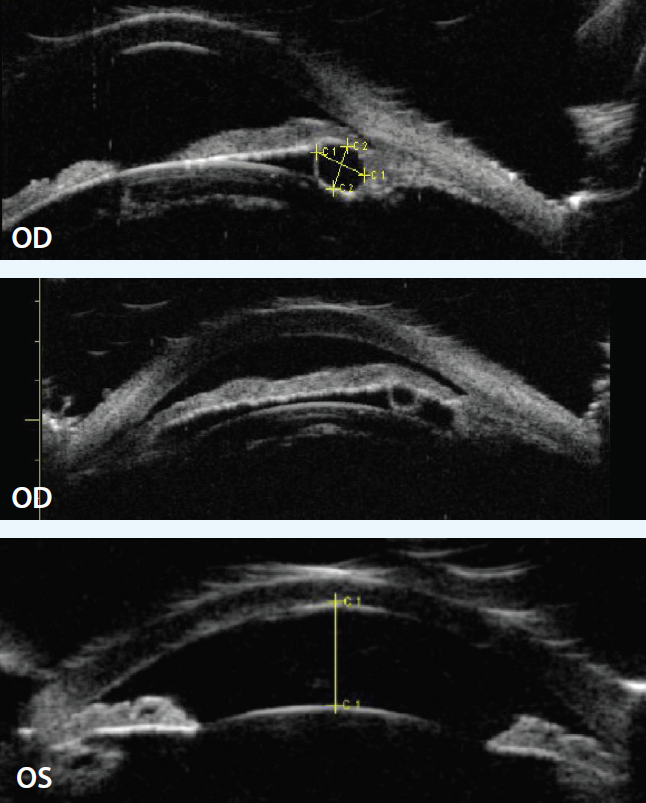

Her BCVA was 20/20 OD and 20/30 OS with a manifest refraction of +1.00 -0.50 × 095 OD and +5.00 -1.50 × 085 OS. Her IOP, as measured by applanation tonometry, was 21 mm Hg OU, and pachymetry demonstrated central corneal thicknesses of 578 µm OD and 611 µm OS. Slit-lamp biomicroscopy was significant only for mild nuclear sclerosis in both eyes. Gonioscopy demonstrated grade 0 angles 360º bilaterally with a lumpy appearance (Figure 1). The posterior segment examination was unremarkable. Soon after the initial exam, she underwent laser peripheral iridotomy of both eyes, and the angles became grade 1.

Figure 1. Gonioscopy demonstrated grade 0 angles 360º OU with a lumpy appearance in both eyes.